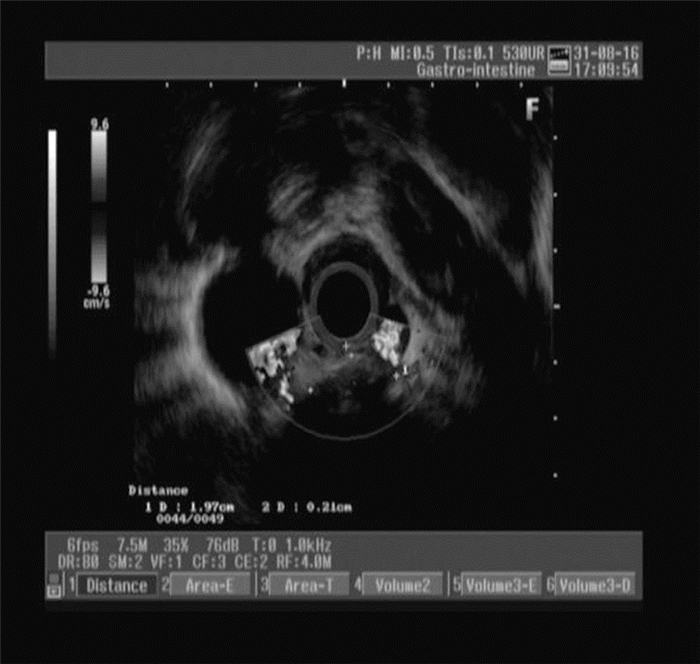

血常规:中性粒细胞百分比84.1%、血小板49×109/L,余正常。尿常规、粪常规、甲胎蛋白、癌胚抗原、糖类抗原199、甲状腺功能、CRP、血清降钙素原正常。乙型病毒性肝炎 (乙肝) 三对、丙型病毒性肝炎 (丙肝) 病毒抗体、抗HIV、血幽门螺杆菌抗体、梅毒特异性抗体、抗核抗体均阴性。A型血、Rh (+)。肝功能:总胆红素44.3 μmol/L、直接胆红素12.1 μmol/L、间接胆红素32.2 μmol/L、ALT 46 U/L、AST 63 U/L、碱性磷酸酶179 U/L、γ-谷氨酰转移酶103 U/L。电解质:钾3.4 mmol/L。凝血常规:凝血酶原时间16.3 s、国际标准化比率1.34、部分凝血活酶时间55.2 s。X线胸片、胸部CT示双肺未见明显异常。上腹部CT示肝硬化、脾大、门脉高压、腹水、胆囊结石并胆囊炎。腹部彩超示肝硬化、脾大、腹腔积液、门静脉内径增宽、胆囊继发改变、胆囊多发结石。胃镜示食管静脉曲张 (轻度)、食管肿物 (表面光滑,未见糜烂及溃疡形成),见图 1。入院诊断“肝硬化失代偿期 (酒精性)、门脉高压症、脾功能亢进症”基本明确,但此次胃镜下发现食管中上段肿物,性质尚不明确,行超声胃镜示食管固有肌层肿物 (考虑间质瘤),见图 2。病理检查结果示 (食管) 小细胞恶性肿瘤、结合免疫组织化学 (组化) 符合小细胞癌。免疫组化结果示CgA (+),CK5/6(-),CKpan (+),K1-67(+50%~75%),LCA (-),NSE (+),P63(-),Syn (+),TTF-1(+),见图 3

图 3 PESCC患者食管肿物 病理结果 (苏木素-伊红染色,×100)

PESCC的临床症状、影像学表现和内镜所见与食管鳞癌、腺癌相似,病理学及免疫组化是确诊本病的金标准。由于胃镜取材组织量小,常有混合细胞类型存在,容易造成误诊而延误治疗,所以PESCC的诊断往往依赖术后的病理结果及免疫组化检测。